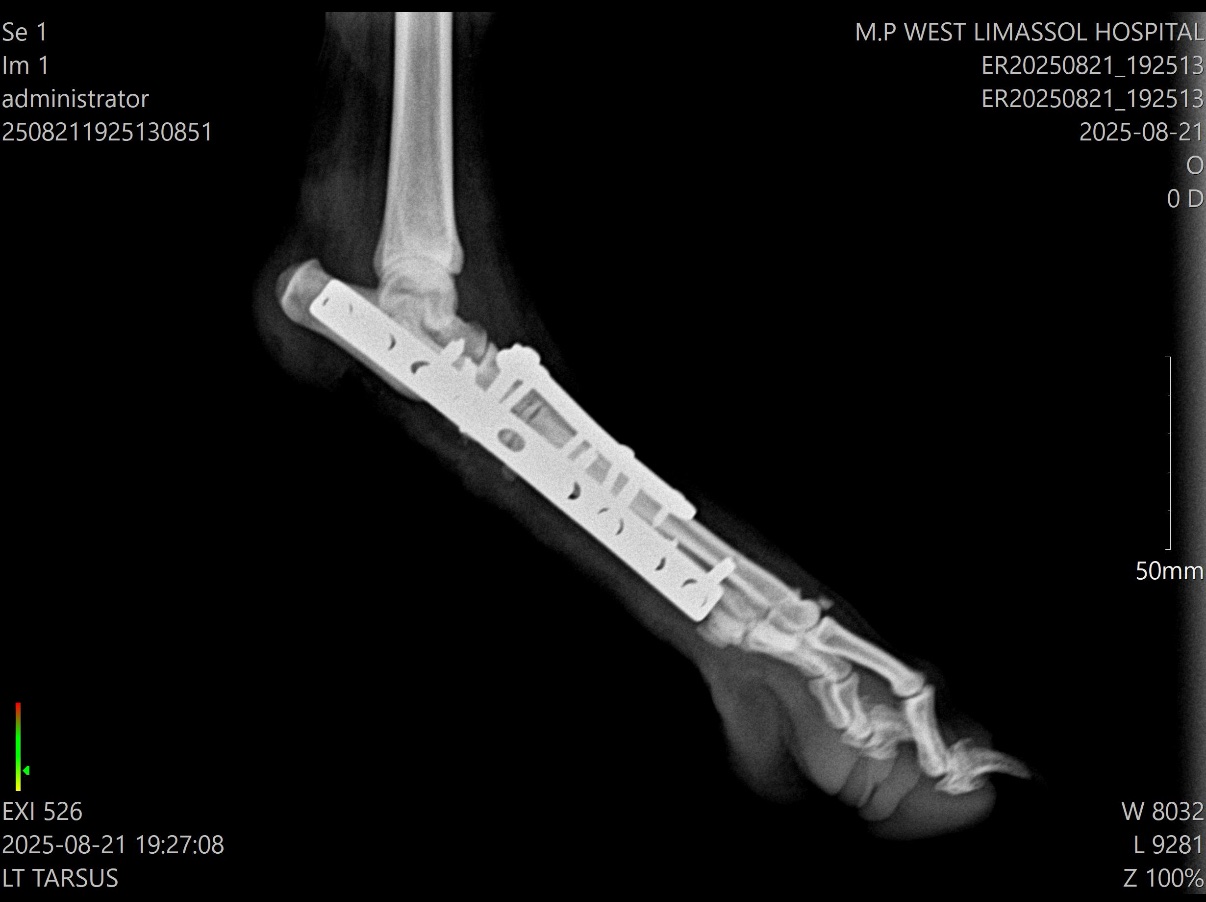

Σχεδιάστηκε μερική αρθρόδεση του ταρσού με σκοπό τη σταθεροποίηση των κατεστραμμένων αρθρώσεων και ταυτόχρονη διατήρηση της λειτουργίας της ταρσοκνημικής άρθρωσης, η οποία είναι απαραίτητη για την απόδοση σε σκύλους εργασίας και άθλησης. Η χειρουργική προσπέλαση περιλάμβανε καθαρισμό των αρθρικών επιφανειών και σταθεροποίηση με δύο πλάκες, τοποθετημένες στρατηγικά ώστε να εξασφαλίσουν μέγιστη βιομηχανική σταθερότητα και να ευνοήσουν την οστική πώρωση. Η χρήση διπλής πλάκας πρόσφερε αυξημένη ακαμψία, μειώνοντας τον κίνδυνο επιπλοκών όπως θραύση υλικών ή καθυστερημένη πώρωση.

Η επέμβαση ολοκληρώθηκε χωρίς επιπλοκές και ο ασθενής ανένηψε ομαλά από την αναισθησία. Η μετεγχειρητική απεικόνιση επιβεβαίωσε τη σωστή θέση των υλικών και την ικανοποιητική ευθυγράμμιση της άρθρωσης. Κατά τη φάση ανάρρωσης εφαρμόστηκε περιορισμένη δραστηριότητα και ελεγχόμενη άσκηση ώστε να διευκολυνθεί η οστική επούλωση με ελάχιστη φόρτιση των υλικών.